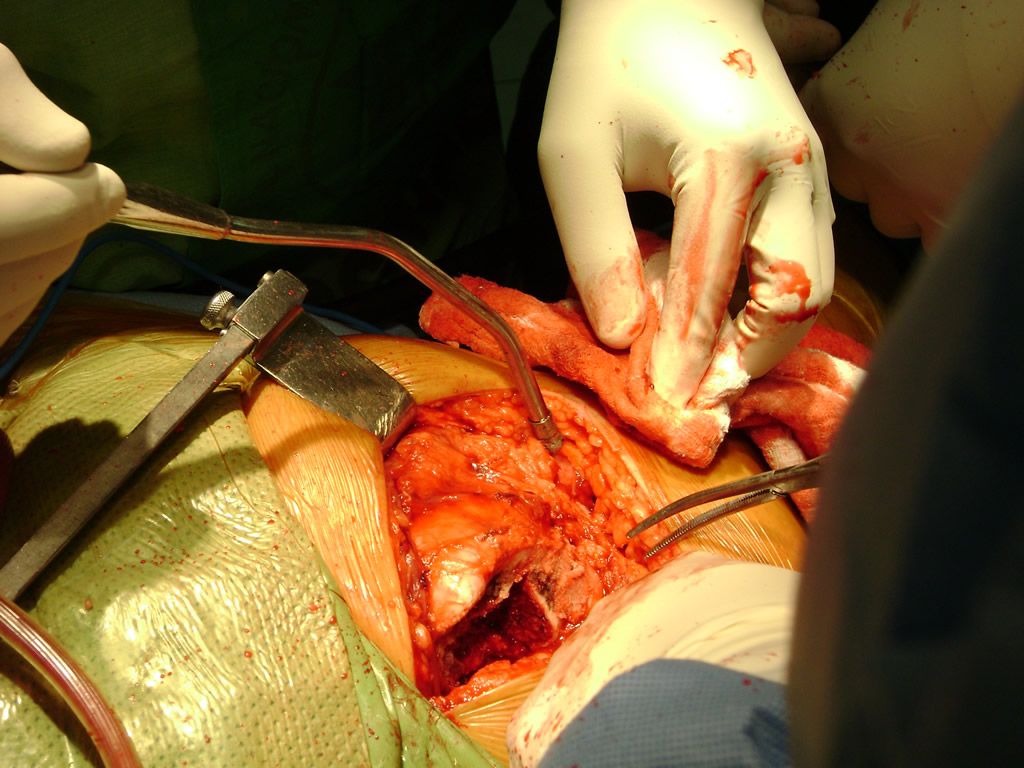

Debido a la fina cobertura de piel que recubre la tibia y el peroné, las fracturas generalmente son abiertas, es decir, el hueso roto rasga la piel, atravesándola. Las fracturas de tibia y peroné generalmente se producen por un fuerte impacto o torsión.

De esta forma nos ponemos a tus órdenes, somos conocedores de estos tipos de problemas, visitarnos será un gusto el poderte ayudar. cualquier inquietud puedes escribirnos al correo Esta dirección de correo electrónico está siendo protegida contra los robots de spam. Necesita tener JavaScript habilitado para poder verlo.